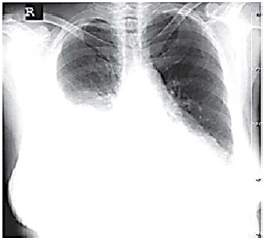

Uma paciente de 68 anos de idade, com queixa principal de falta de ar, tosse e dor torácica, relata ter iniciado, em fevereiro de 2019, quadro de tosse produtiva com escarro amarelado, febre, inapetência e dispneia aos grandes esforços. Houve piora evolutiva da tosse, além do aparecimento de dor torácica em topografia de base de hemitórax direito. A paciente é hipertensa e diabética e está em uso de enalapril, indapamida e metformina. Nega história de etilismo ou tabagismo. Ao exame físico, a paciente se encontrava hemodinamicamente estável, em regular estado geral, taquipneica (32 ipm), hipocorada (+/++++), normotensa e com oximetria periférica de 95% em ar ambiente. Na ausculta pulmonar, apresentou crepitações difusas em hemotórax direito. O aparelho de raio X estava quebrado. O hemograma evidenciou: leucócitos 14.500/mm3, com 3% de bastões; 30,4% de hematócrito; plaquetas 320.000/mm3; ureia 22 mg/dL; creatinina 0,5 mg/dL; glicemia 250 mg/dL; sódio 140 mEq/L; e potássio 4,5 mEq/L. Foram prescritos para uso domiciliar amoxicilina e clavulanato 500/125 mg, de oito em oito horas, por catorze dias e a paciente foi orientada a retornar em 72 h se não houvesse melhora dos sintomas.